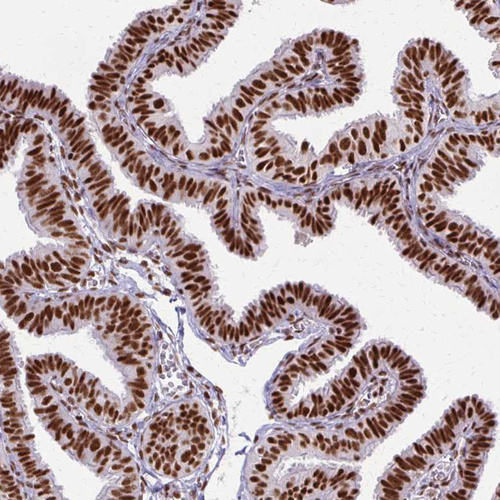

Immunohistochemical staining of human fallopian tube, kidney, lymphoid tissues and testis using Anti-XRCC6 antibody HPA062226 (A) shows similar protein distribution across tissues to independent antibody HPA047549 (B).